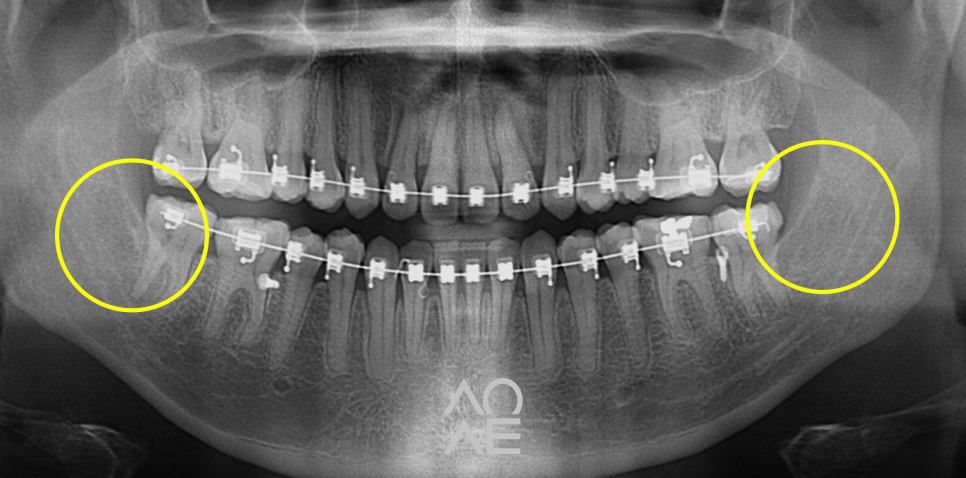

위 주소로 내원하신 학생분이신데요

저희 치과에서 교정을 하고 계셔서

사랑니의 존재는 익히 알고 있었는데요

파노라마라고 불리는 X-ray 를 보니

걱정하신 것 만큼 심각한 상황도 아니라서

당일 발치를 진행하였습니다

24.6.29

5분만에 발치하였습니다!

| 발치 전 | 발치 후 |